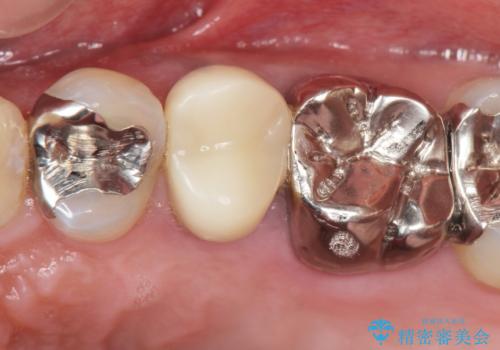

セラミックインレーと根管治療を伴うセラミッククラウン